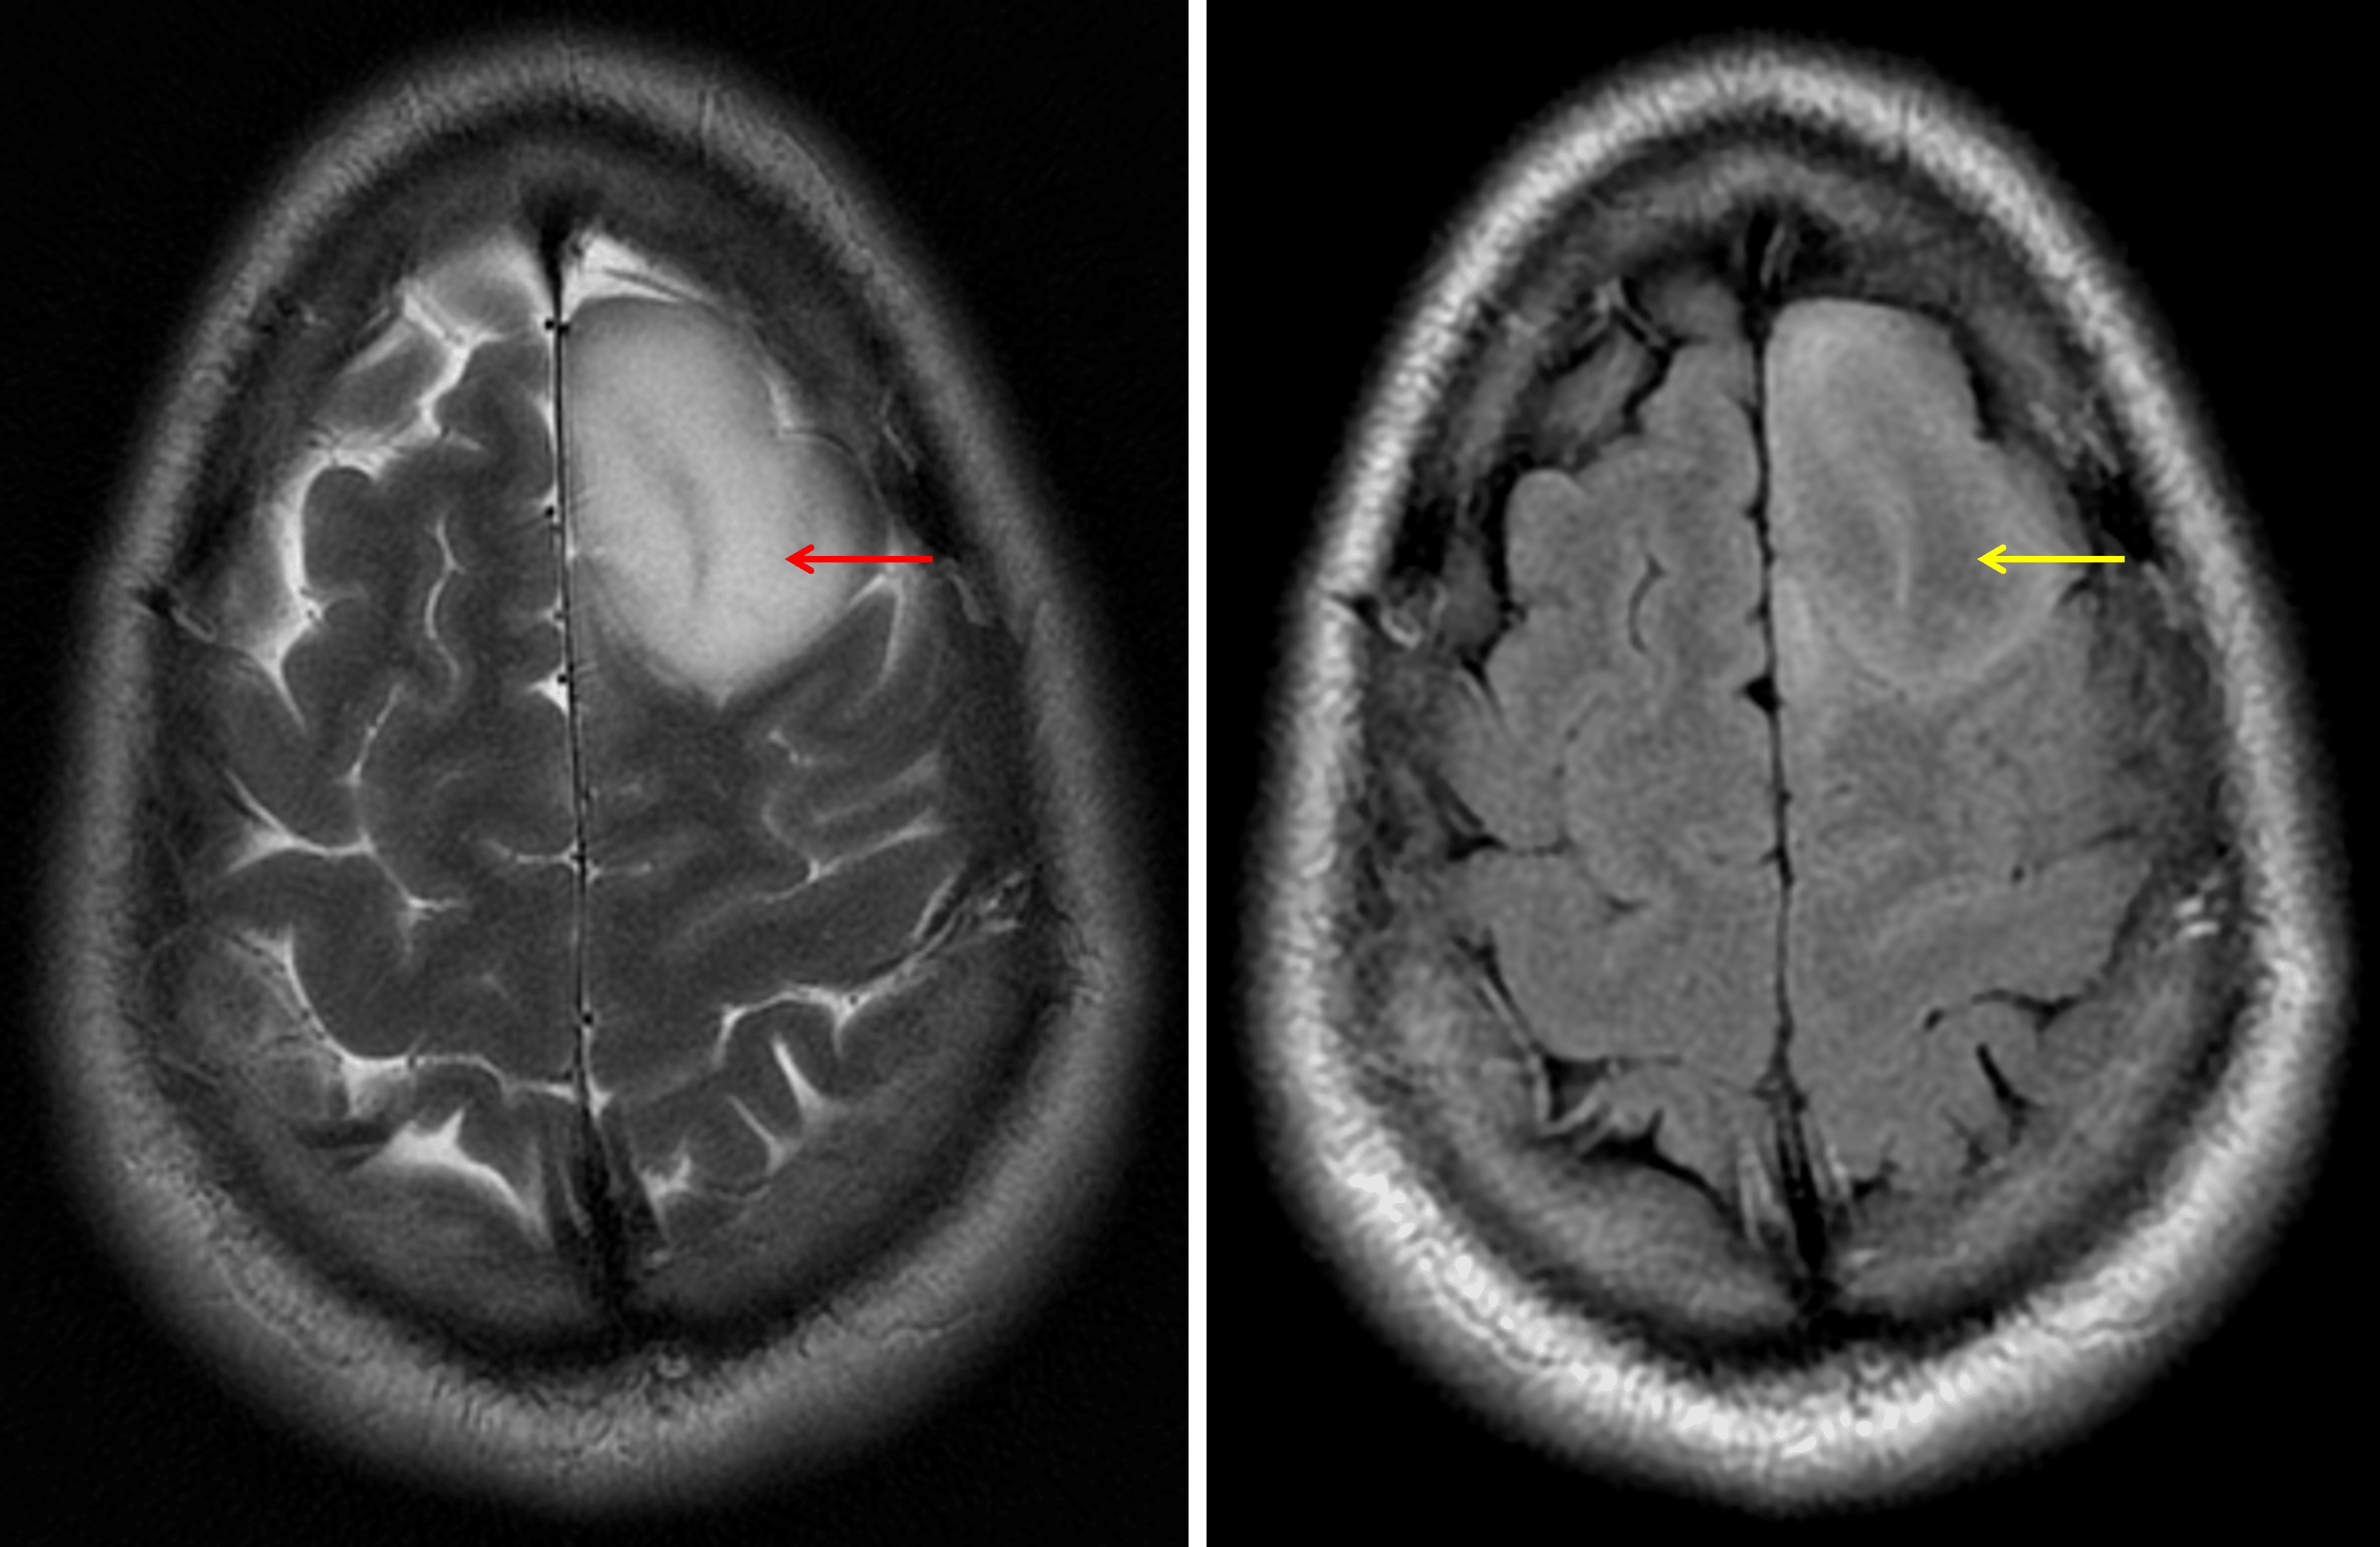

• T1 hypointense, T2 hyperintense expansile mass extending to the cortex in the left superior frontal gyrus

• Mixed hyperintense and isointense internal FLAIR signal

• No corresponding enhancement, restricted diffusion, or susceptibility artifact

• Mild corresponding local mass effect without midline shift or evidence of herniation or hydrocephalus

The T2-FLAIR mismatch sign: the lesion demonstrates internal T2 signal hyperintensity (red arrow) contrasted to relatively hypointense FLAIR signal (yellow arrow).